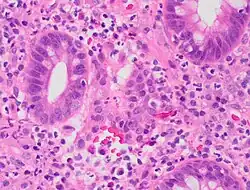

| A micrograph demonstrating cryptitis, a microscopic correlate of colitis. H&E stain. | |

An important investigation in the assessment of colitis is biopsy for histopathology. A very small piece of tissue (usually about 2mm) is removed from the bowel mucosa during endoscopy and examined under the microscope by a histopathologist. A biopsy report generally does not state the diagnosis, but should state any presence of chronic colitis, give an indication of disease activity, as well as state the presence of any epithelial damage (erosions and ulcerations).[6]

Histopathology findings generally associated with chronic colitis include:[6]

Crypt degeneration -

Crypt branching and other architectural distortions -

Paneth cell (pictured) or gastric metaplasia (only applies in the left colon and rectum)

Other findings include basal plasmacytosis and mucin depletion.[6] Histopathology findings generally associated with active colitis include:[6]

-

Neutrophilic cryptitis (neutrophils within crypt epithelium) -

Crypt abscesses (luminal neutrophilic aggregates) -

Gland destruction -

Ulceration (seen here as absence of epithelium, and granulation tissue with many fibroblasts)